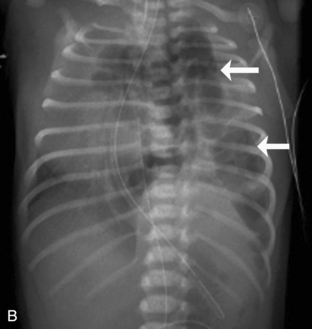

The aortic knob and the trachea will be displaced if a mediastinal shift occurs. When significant atelectasis is present, the trachea and aortic knob usually are displaced toward the area of collapse, because of the volume loss associated with the atelectais.22 However, if a large pleural effusion or pneumothorax is present, the trachea and aortic knob typically will be displaced away from the involved lung and toward the unaffected side, because these problems represent volume gain in the chest (Fig. 10-10).

image

Fig. 10-10 Tension pneumothorax. This 5   month old with complex congenital heart disease was noted by the nurse to have respiratory distress, including tachypnea and nasal flaring. The nurse also noted decreased breath sounds and chest expansion in the left chest and tracheal deviation to the right. This supine anteroposterior film was obtained and demonstrated a left-sided tension pneumothorax (white arrows). The trachea (black arrow) and aortic knob are displaced away from the involved left hemithorax and toward the unaffected right side because of the increased volume associated with the pneumothorax.